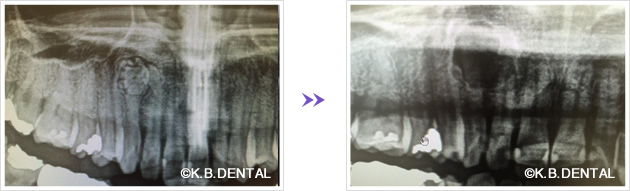

術後2年経過の最も典型的なエナメル上皮種です。再発率が非常に高いので最低でも5年以上の経過観察が必要となります。今回は摘出術と一部健常域まで辺縁切除(骨を削る)を行いました。

1枚目(パノラマ)上:術前 下:術後 摘出部分に新生骨を認めます。

2枚目(CT)上:術前 下:術後 摘出部分に新生骨を認めます。

3枚目 左:摘出物の腫瘍本体と割断像 右:割断して内容物が充実性である事がわかります。

4枚目 上:高倍率 下:低倍率 腫瘍実質の胞巣が濾胞状を示しているのがわかります。